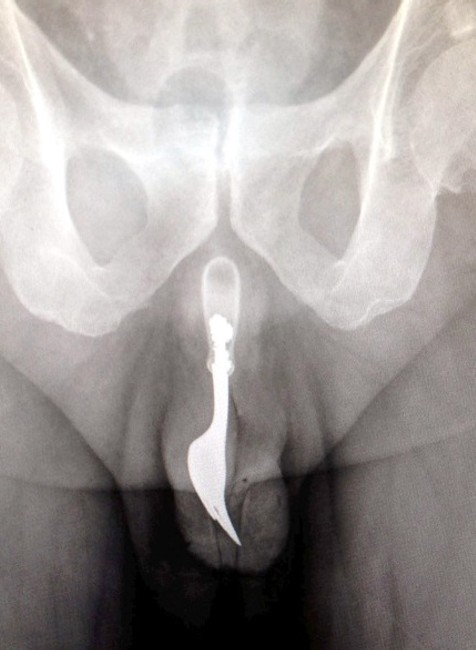

CANBERRA / Keď lekári prijali na pohotovosti v Austrálii staršieho pacienta, ktorý sa sťažoval na krvácanie z pohlavného orgánu, to ešte netušili, čo mu v ňom nájdu. Rontgenová snímka ich musela šokovať! V penise mal totiž strčenú 10 cm dlhú, oceľovú kuchynskú vidličku! A pravda o tom, ako sa mu tam dostala, nenechala na seba dlho čakať...

Lekári z austrálskej Canberry sa rozhodli zverejniť jeden z kontroverzných prípadov, kedy z pacientovho tela museli chirurgicky odstraňovať cudzí objekt. Nielen z tela, ale rovno z jeho pohlavného orgánu! Išlo pritom o 70-ročného muža, ktorý sa napokon ku všetkému priznal.

Podľa lekárskej správy, ktorú zverejnil denník The Daily Mail, sa muž chcel sexuálne uspokojiť, no jeho sexuálne dobrodružstvo vypálilo horšie, než čakal. Vidlička mu totiž ostala strčená v tele a spôsobila obrovské bolesti. Aj napriek nim sa však zahanbený dôchodca odvážil lekársku pomoc vyhľadať až o 12 hodín! Lekári muža napokon uspali a vidličku odstránili aj za použitia lubrikantu a pinzety... Procedúra bola úspešná a krátko po operácii mohol muž opustiť bez vážnych následkov nemocnicu.